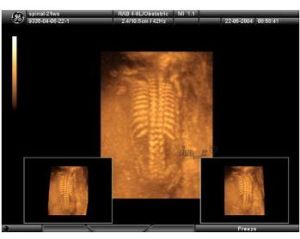

2、活動期體徵可見顱骨軟化(桌球頭)、方顱、前囪遲閉、出牙延遲、肋骨串珠、肋外翻、肋隔溝、雞胸、漏斗胸、手鐲、鐲繞,“O”形腿、“X”形腿、脊柱後突或側彎等。